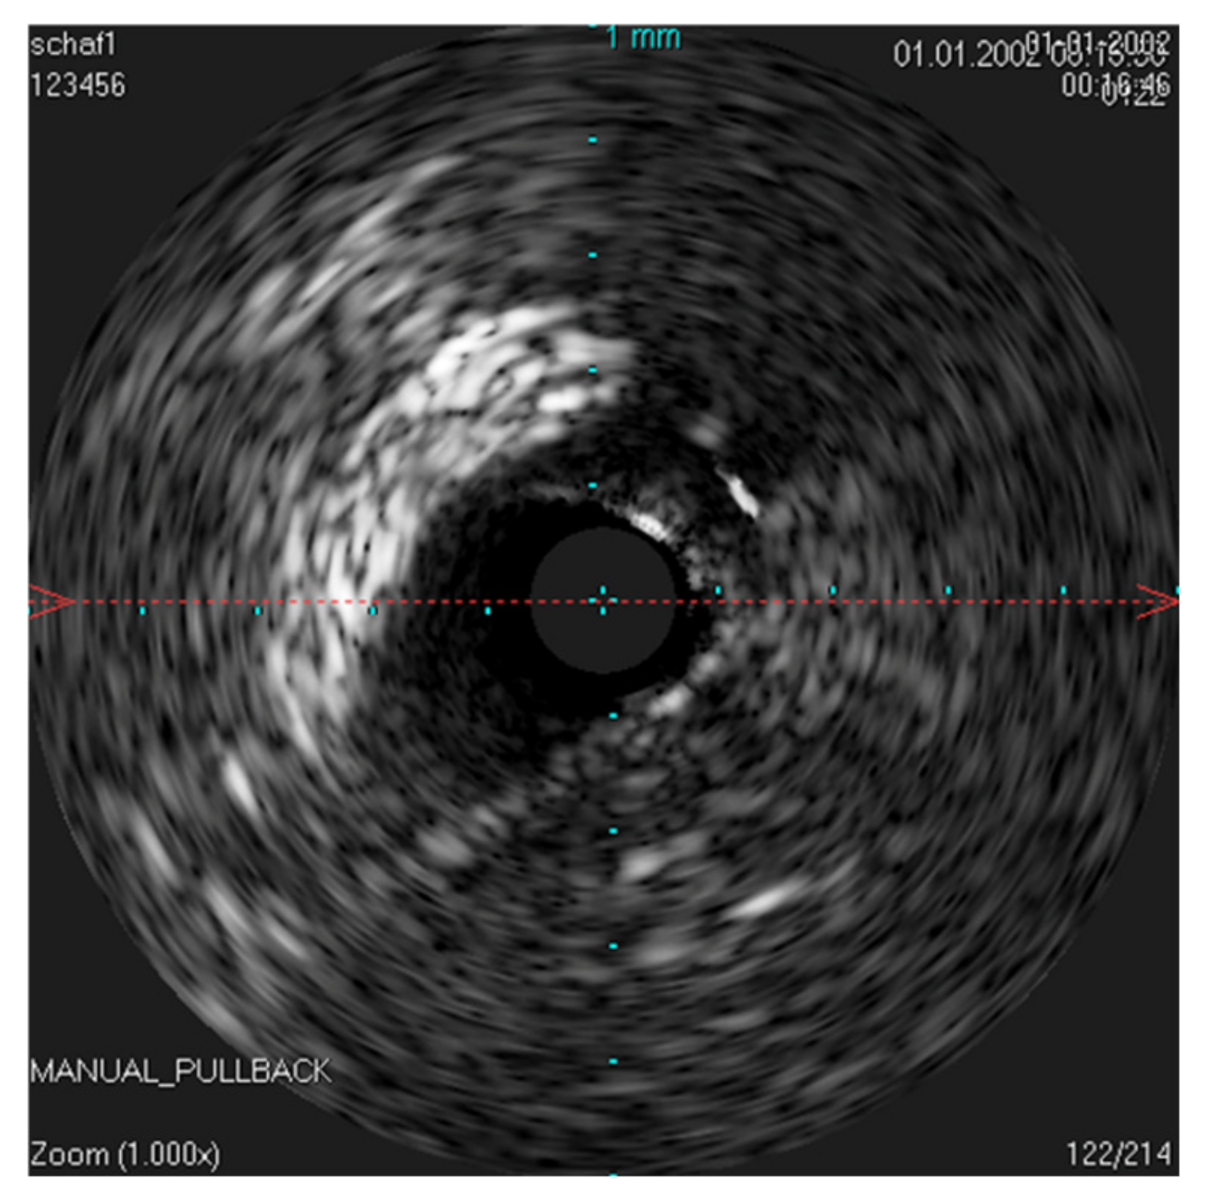

The IVUS provided a good image of the slit-formed shape of the ET (Figure 1) and the bony part with the isthmus (Figure 2) in the cross-section view. Bony structures and cartilage can be distinguished from the muscles and the Ostman fat pad. The signal transmission from the catheter to the tissue appeared to be good in all cases, even though the mucosal layer also caused some intense reflections. By flushing the ET with water (Figure 3), the lumen was more visible and became spindle shaped. Reflections at the mucosal layer were reduced.

The scan of the native ET achieved good results, although minor artifacts occurred, probably because the sound coupling was disturbed by air bubbles. By flushing the ET with water, it was possible to produce a consistently good image, indicating a better coupling. At the same time, the tube unfolded and the lumen appeared spindle-shaped. Scanning the ET in vivo without adding a coupling substance resulted in scans of good quality. This could probably still be improved if a sterile liquid, for example, physiologic saline or ultrasound gel, could be instilled into the ET by means of a catheter. Care should be taken that no pathogens are introduced and that the middle ear is not flooded. Otherwise, there is a risk of infections of the middle ear and ruptures of the tympanic membrane.